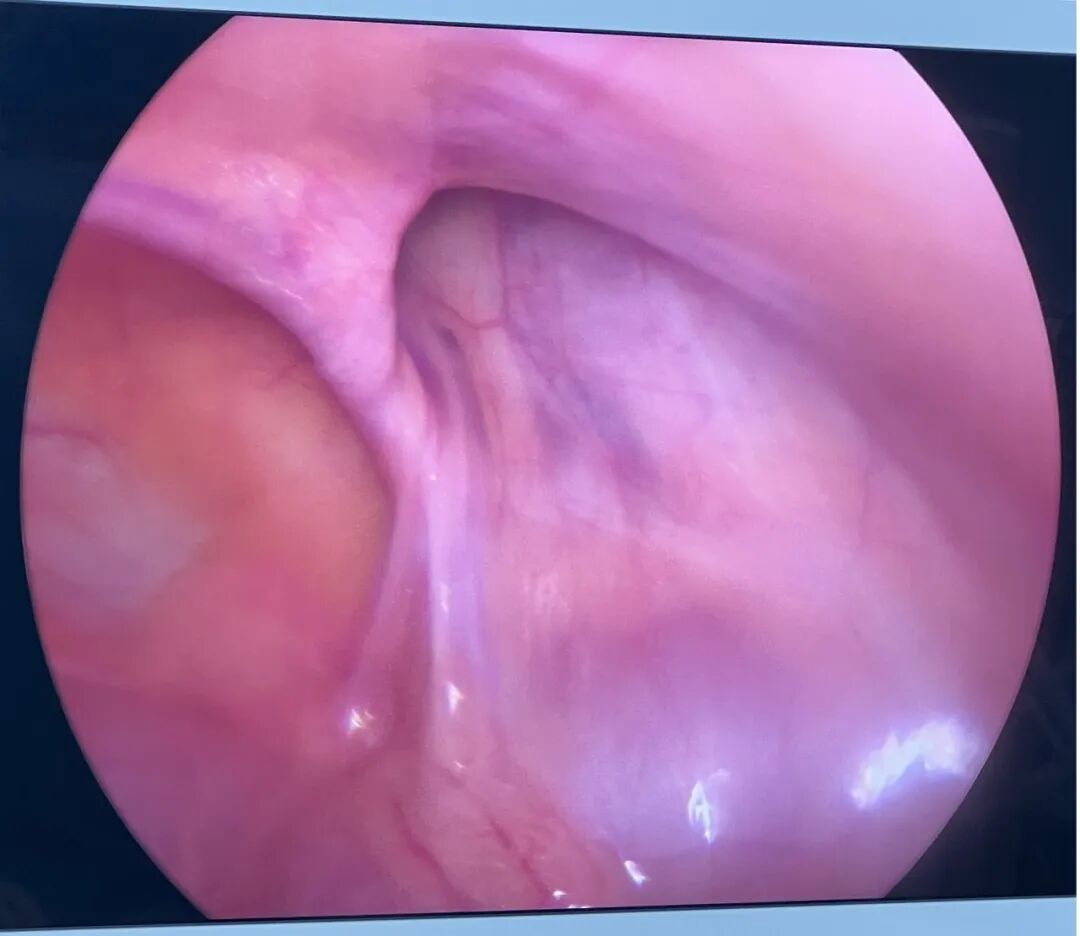

腹腔内表现为腹股沟区存在一个洞,该洞与体表或阴囊相通。

当患儿哭闹、咳嗽、用力排便时,腹压增高,腹腔内容物(如肠管、大网膜、卵巢、膀胱等)掉入腹股沟区的缺损,在体外“鼓包”。

当疝内容物被卡在腹股沟区缺损处无法回纳时,即发生“嵌顿”。